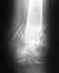

После длительного лечения у меня был следующий диагноз диагноз: неправильно сросшийся оскольчатый внутрисуставной перелом левой пяточной кости, подвывих костей левой стопы в суставе Шопара. Я хотол узнать, можно ли прооперировать ногу и собрать кости правильно. Также у меня консолидированые переломы обоих локтевых отростков и они неправильно сраслись, врезультате у меня не полностью разгибаются руки. Можно ли руки тоже прооперировать что-бы они до конца разгибались.

Вероятно, как-то можно попытаться помочь и там, и там. Для принятия решения нужно обратиться очно в отделение соответствующего профиля, имея свежие (и лучше бы еще и прежние) рентгенограммы.